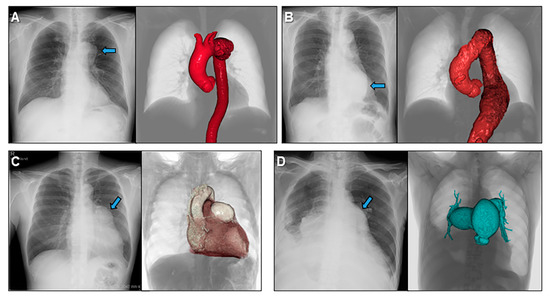

4. Educational Implication of the Three-Dimensional Living Heart Anatomy

5. Clinical Implication in Acquired Heart Disease with Representative Cases